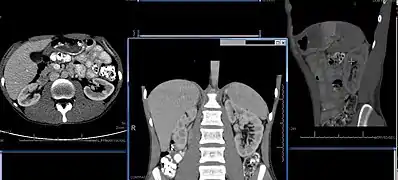

Imaging

Renal ultrasonography is essential in the diagnosis and management of kidney-related diseases.[44] Other modalities, such as CT and MRI, should always be considered as supplementary imaging modalities in the assessment of renal disease.[44]